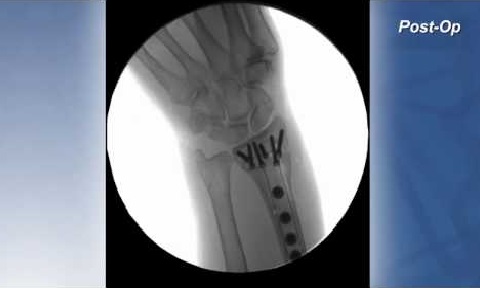

CASE STUDY Distal Radius Fracture

Dr. Adam Rives, M.D. describes the outcomes of an elderly smoker patient who was implanted with a distal radius plate composed of PEEK-OPTIMA Ultra-Reinforced